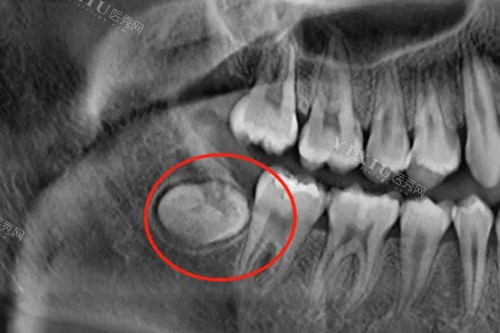

随着年龄的增长,有些人可能会发现自己的智齿开始生长。然而,智齿并非总是以正确的方式生长,横生智齿就是其中一种常见情况。横生智齿是指智齿在横向方向上生长,与其他牙齿产生冲突。虽然这可能引起疼痛和口腔不适,但并非所有横生智齿都需要拔除。

横生智齿通常具有以下特征:生长方向不正确,与其他牙齿发生冲突,无法顺利咬合。因为横生智齿可能导致牙齿移位、口腔感染、牙龈肿痛等问题,所以一些人可能会考虑拔除它们。然而,拔除横生智齿并非总是必要的选择。